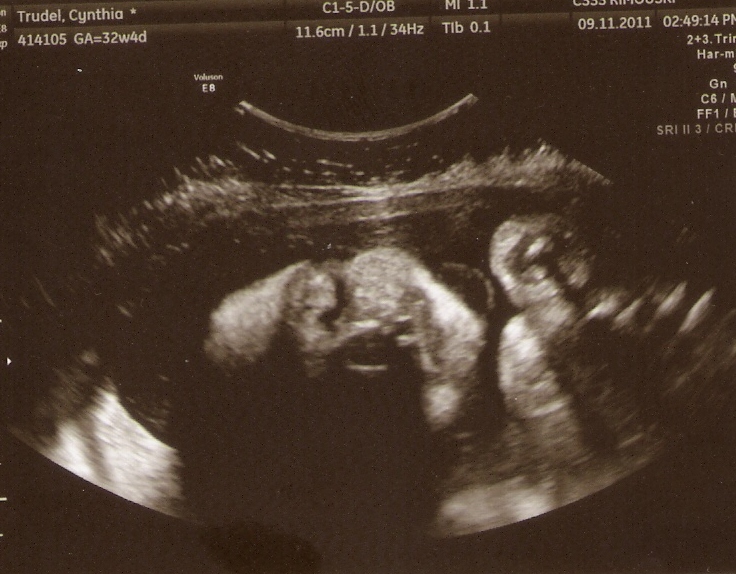

Comment en sommes-nous arrivés à cette journée dans ce bureau du CHUL? La semaine précédente, nous avions une échographie à l’hôpital de Rimouski. La grossesse avançait bien et nous étions déjà à la 28e semaine. La gynécologue avait détecté quelque chose d’anormal au cœur, mais la technologie moins avancée au CHRR a fait en sorte que nous avons dû nous rendre à Québec la semaine suivante. Après un écho du cœur du bébé de près de 2 heures, le verdict tombait comme une tonne de brique : sténose aortique. Après une bonne rencontre avec la cardiologue, d’autres tests nous attendaient. Il fallait s’assurer que, du côté génétique, tout était beau, que bébé n’avait pas de syndrome qui aurait pu causer cette malformation cardiaque. Ma copine dû se prêter à une amniocentèse qui permet de dépister bien des syndromes. Pour ceux qui ne savent pas ce qu’est une amniocentèse, on rentre une longue aiguille dans la bedaine de la future maman pour prélever du liquide amniotique. Cette procédure peut aussi entrainer des possibilités de contraction et de fausses couches. Et c’est ce qui arriva au retour à la maison le lendemain après une autre série de rendez-vous le matin. Heureusement, les contractions, quoique très fortes, n’auront pas « causé de dégâts ». Ma copine aura malgré tout eu la « chance » de passer une nuit en observation à l’hôpital! Deux jours chargés d’émotion…